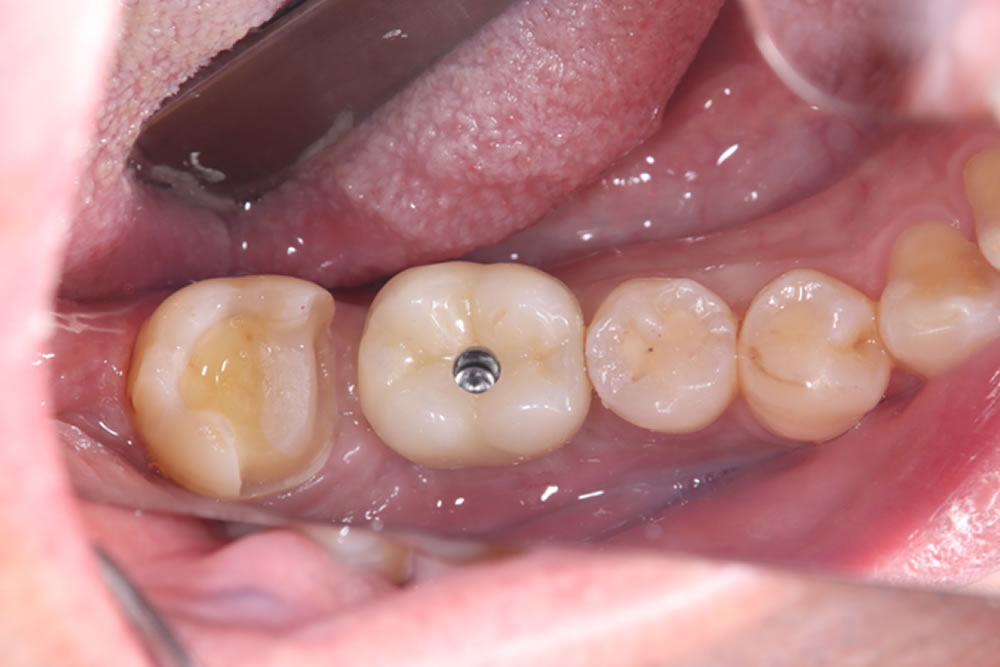

最終的な上部構造(人工歯)を装着・治療完了

プロビジョナル(精密仮歯)での経過が問題なかったため、最終的な上部構造(人工歯)を作製・装着し、治療完了となりました。

治療前後の比較

インプラント治療により、固いものもしっかり噛めるようになったとのことでした。また、歯肉移植を併用したことで、インプラント周囲の清掃性も向上しました。